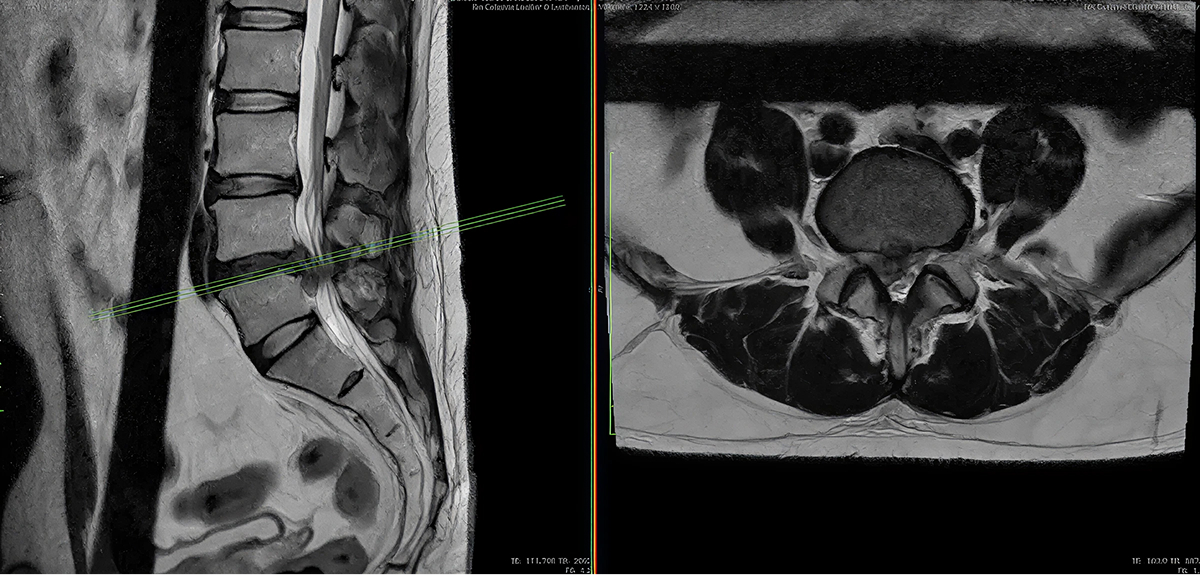

Columna lumbar

La lumbalgia (dolor lumbar o dolor en la parte baja de la espalda) es una de las causas más frecuentes de consulta médica. De hecho, a lo largo de la vida, se estima que entre 70% y 85% de las personas experimentarán al menos un episodio de lumbalgia en algún momento de su vida. Las causas pueden ser diversas, pero dentro de los principales factores de riesgo, existen cambios degenerativos, malas posturas y otras causas secundarias a lesiones biomecánicas de la columna vertebral, entre otras.

La columna lumbar corresponde a las vértebras bajas de la espalda (normalmente L1-L5). Esta región, sometida a gran carga mecánica, permite la movilidad del tronco, soporta el peso corporal y protege las raíces nerviosas que se dirigen hacia las piernas y la estructura pélvica. Cuando la anatomía o la función se alteran, puede surgir dolor lumbar, irradiación al miembro inferior, entumecimiento, debilidad, alteraciones de la marcha o pérdida de control de esfínteres, en casos severos.

- Diagnóstico preciso: mediante resonancia magnética, tomografía, estudios de conducción nerviosa y valoración clínica por nuestro equipo multidisciplinario.